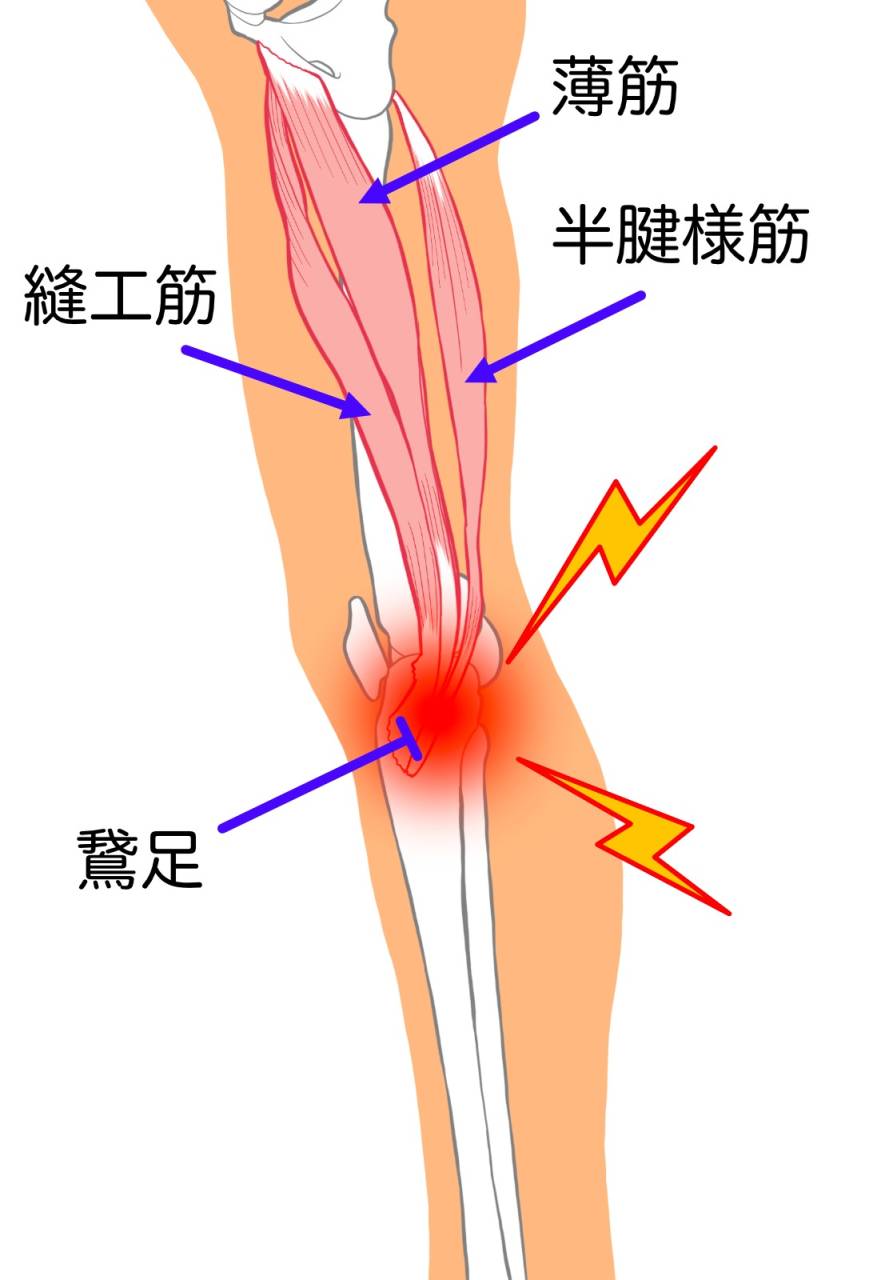

- 膝の痛み

- 痛み

- スポーツ

- 足の痛み